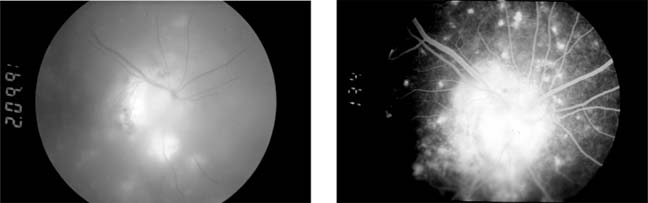

Central Retinal Vein Occlusion (new window  Figure 15-7)

Figure 15-7

Figure 15-7: Central retinal vein occlusion. Left: Photograph shows linear hemorrhages in the nerve fiber layer and punctate hemorrhages in the deeper retinal layers. Right: Fluorescein angiogram shows dilation of the veins.

Fundus examination shows dilated tortuous veins with retinal and macular edema, hemorrhages all over the posterior pole, and cotton-wool spots. The arterioles are usually attenuated, indicating generalized microvascular disease.

The prognosis for vision is poor. Fluorescein angiography demonstrates two types of response: a nonischemic type, with dilation of retinal vessels and edema; and an ischemic type, with large areas of capillary nonperfusion or evidence of retinal or anterior segment neovascularization. In 93% of ischemic and 50% of nonischemic central retinal vein occlusions, the ultimate visual acuity is less than 20/200.

Central retinal vein occlusion has an increased incidence in certain systemic conditions such as diabetes mellitus, hypertension, collagen vascular diseases, and hyperviscosity syndromes (eg, Waldenström's macroglobulinemia, angioimmunoblastic lymphadenopathy). However, the prevalence of cerebrovascular or cardiovascular disease is not increased compared to the general population. Investigations include measurement of serum lipids, plasma proteins, plasma glucose, and assessment of blood viscosity by hemoglobin, hematocrit, and fibrinogen estimations. In young patients, protein C, activated protein C resistance, protein S, and antithrombin III levels should be measured to exclude abnormalities of the thrombolytic system. If hypertension is present, simple renal function tests, including urea and electrolytes, estimation of creatinine clearance, microscopic examination of the urine, and renal ultrasound are indicated.

Treatment of retinal vein occlusion is unsatisfactory. Trials with anticoagulants and fibrinolytic agents have not been successful. In ischemic central retinal vein occlusion, panretinal laser photocoagulation is effective in preventing and treating secondary neovascular glaucoma.

Occasionally, central retinal vein occlusion occurs in young people and may be associated with cells in the vitreous. Rheologic investigations are usually negative, and the prognosis for vision is good.